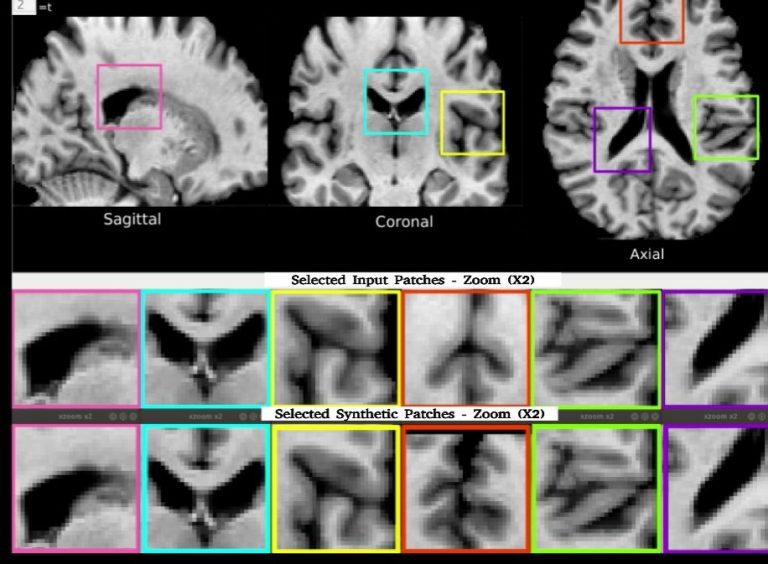

La diffusione di modelli generativi profondi ha portato alla creazione di dati sintetici per l’imaging...